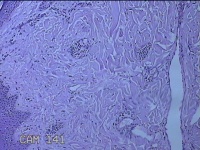

头皮结节

性别

男

年龄

33岁

临床诊断

皮肤赘生物

一般病史

发现头皮结节半个月余,无明显疼痛及不适。

标本名称

大体所见

灰白暗红色带皮肤样结节1x0.8x0.3cm一个,表面糜烂,切开结节呈实性,切面灰白粉红色,质软。

看不清,可能是毛细血管瘤,技术很需提高,不然迟早会。。。